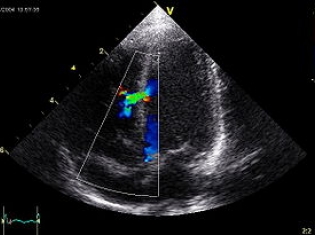

In addition to pulmonary atresia, there is also 3. ventricular septal defect (VSD, a hole in the wall between the two outflow chambers of the heart), and 4. overriding aorta (aorta positioned over the VSD instead of the left ventricle, the outflow tract of oxygenated blood to the body). These latter two defects cause further difficulty in getting oxygenated blood to the tissues, with the VSD causing oxygenated blood to mix with de-oxygenated blood (diluting it), and the position of the overriding aorta causes this diluted blood to be sent out to the body more than fully oxygenated blood from the left ventricle. Depending on the severity of the defect, babies can be symptomatic for a while and learn techniques for relief such as squatting or medications, but ultimately, total surgical repair is needed.

The most common non-cyanotic congenital heart defect is the ventricular septal defect. This accounts for 30%-60% of all congenital heart defects, and occurs every 2-6 live births per 1000. In this defect, the right and left ventricles have a hold between them, a failure of the wall to close during gestation. Because of blood pressures, it causes blood from the left heart to be pushed into the right heart and back to the lungs. This can cause several problems, most notably pulmonary hypertension in the lungs (high blood pressure), as well as overworking the left ventricle (which can cause eventual heart failure). Patients who have a VSD may not have any symptoms for a long time, but when they do, it's typically shortness of breath, hard and fast breathing, and a failure to thrive if it's a baby. Similarly, there can also be a hole in the wall between the two atria, an atrial septal defect. This is more rare, and may not present until much later in life. Again, they cause blood to move from the left heart into the right, and can put too much pressure on the lungs, and eventually cause atrial fibrillation (and the strokes that come with it) in adults, congestive heart failure, and pulmonary hypertension.